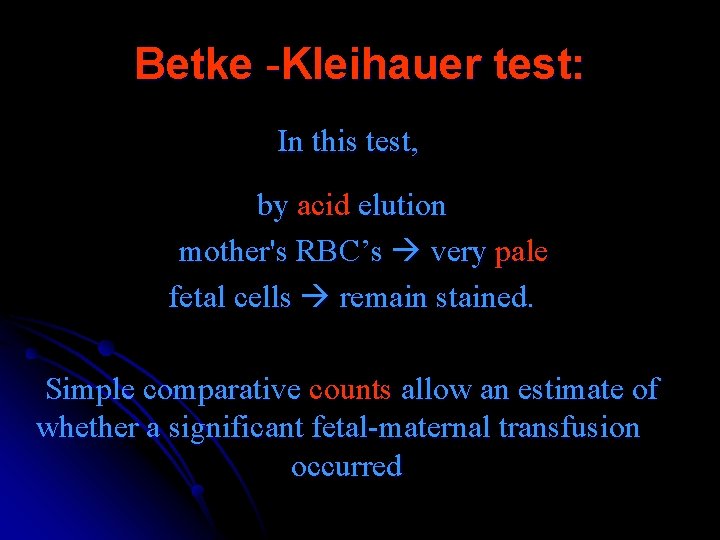

Betke -Kleihauer test: In this test, by acid elution mother's RBC’s very pale fetal cells remain stained. Simple comparative counts allow an estimate of whether a significant fetal-maternal transfusion occurred